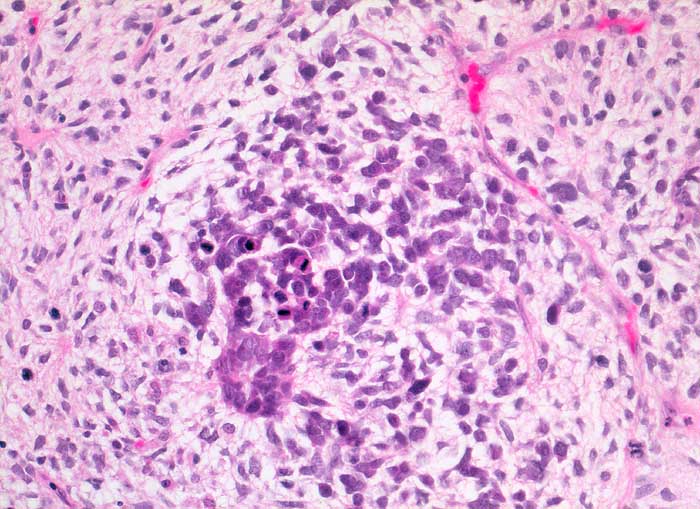

PathoPic ID 5385 - maligner Müller'scher Mischtumor: Sarkomkomponente

maligner Müller'scher Mischtumor: Sarkomkomponente

Sarkomatöse Komponente mit zahlreichen Mitosen